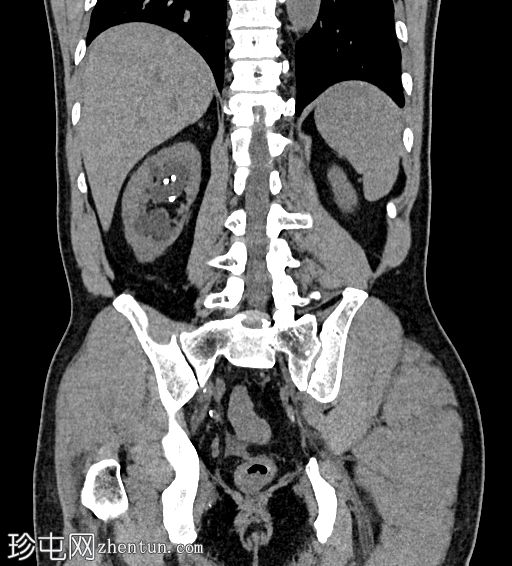

CT扫描

冠状位

平扫

可见中度右肾积水和输尿管积水。右肾双极长10.6厘米。可见输尿管支架,近端位于肾上极肾盏,远端位于膀胱内。肾下极可见肾结石。肾下极可见肾皮质囊肿,囊壁薄,内含钙化。肾上极可见肾实质钙化。在支架旁远端输尿管(S1至S2椎体水平)可见少量输尿管结石。

左肾双极长9.2厘米。肾上极和肾下极可见微小结石。未见输尿管结石。无肾积水或输尿管积水。肾上极可见肾皮质囊肿。

膀胱轮廓正常。未见膀胱结石。